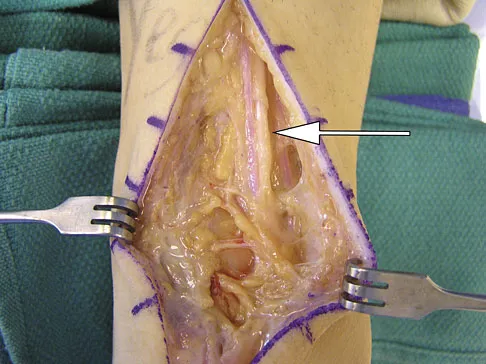

A 22-year-old right hand-dominant man who fell off his motorcycle onto the tip of his right shoulder 2 weeks ago now reports pain and difficulty raising his right arm. Examination reveals tenderness and gross movement over the lateral scapular spine and severe weakness during resisted abduction. A radiograph and 3D-CT scan are shown in Figures 24a and 24b. What is the next most appropriate step in management?

Explanation